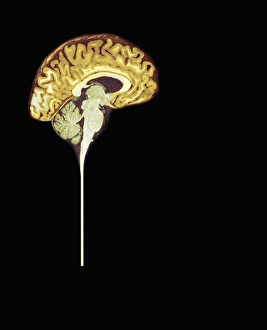

The central nervous system, the intricate network that governs our every thought and movement, is a marvel of complexity. From the delicate cerebellum tissue to the detailed light micrograph capturing its essence, we are reminded of its importance in maintaining balance and coordination. Anatomy comes alive as we explore the human brain from an inferior view. The intricacy of brain fibers is revealed through DTI MRI scans like C017/7099 and C017/7035, showcasing their vital role in transmitting information throughout this extraordinary organ. Artistic renderings bring us closer to understanding the medulla oblongata's significance within the brain. Its portrayal in various artworks allows us to appreciate how it controls essential functions such as breathing and heart rate. As we delve deeper into studying the central nervous system, models of the human brain provide invaluable insights into its structure and organization. Lateral views reveal countless regions responsible for cognition, emotion regulation, sensory perception, and motor control. Microscope slides offer glimpses into nerve cells' intricate architecture—a testament to their ability to transmit electrical signals at lightning speed. Meanwhile, glial stem cell cultures captured under a light microscope remind us of their crucial role in supporting neuronal function. Finally, artistic representations unveil the limbic system's enigmatic nature—an interconnected web responsible for emotions and memory formation. These captivating artworks allow us to visualize this complex network within our brains. Exploring these hints provides a glimpse into the awe-inspiring world of our central nervous system—the very foundation upon which our thoughts, actions, memories reside—reminding us just how remarkable our brains truly are.